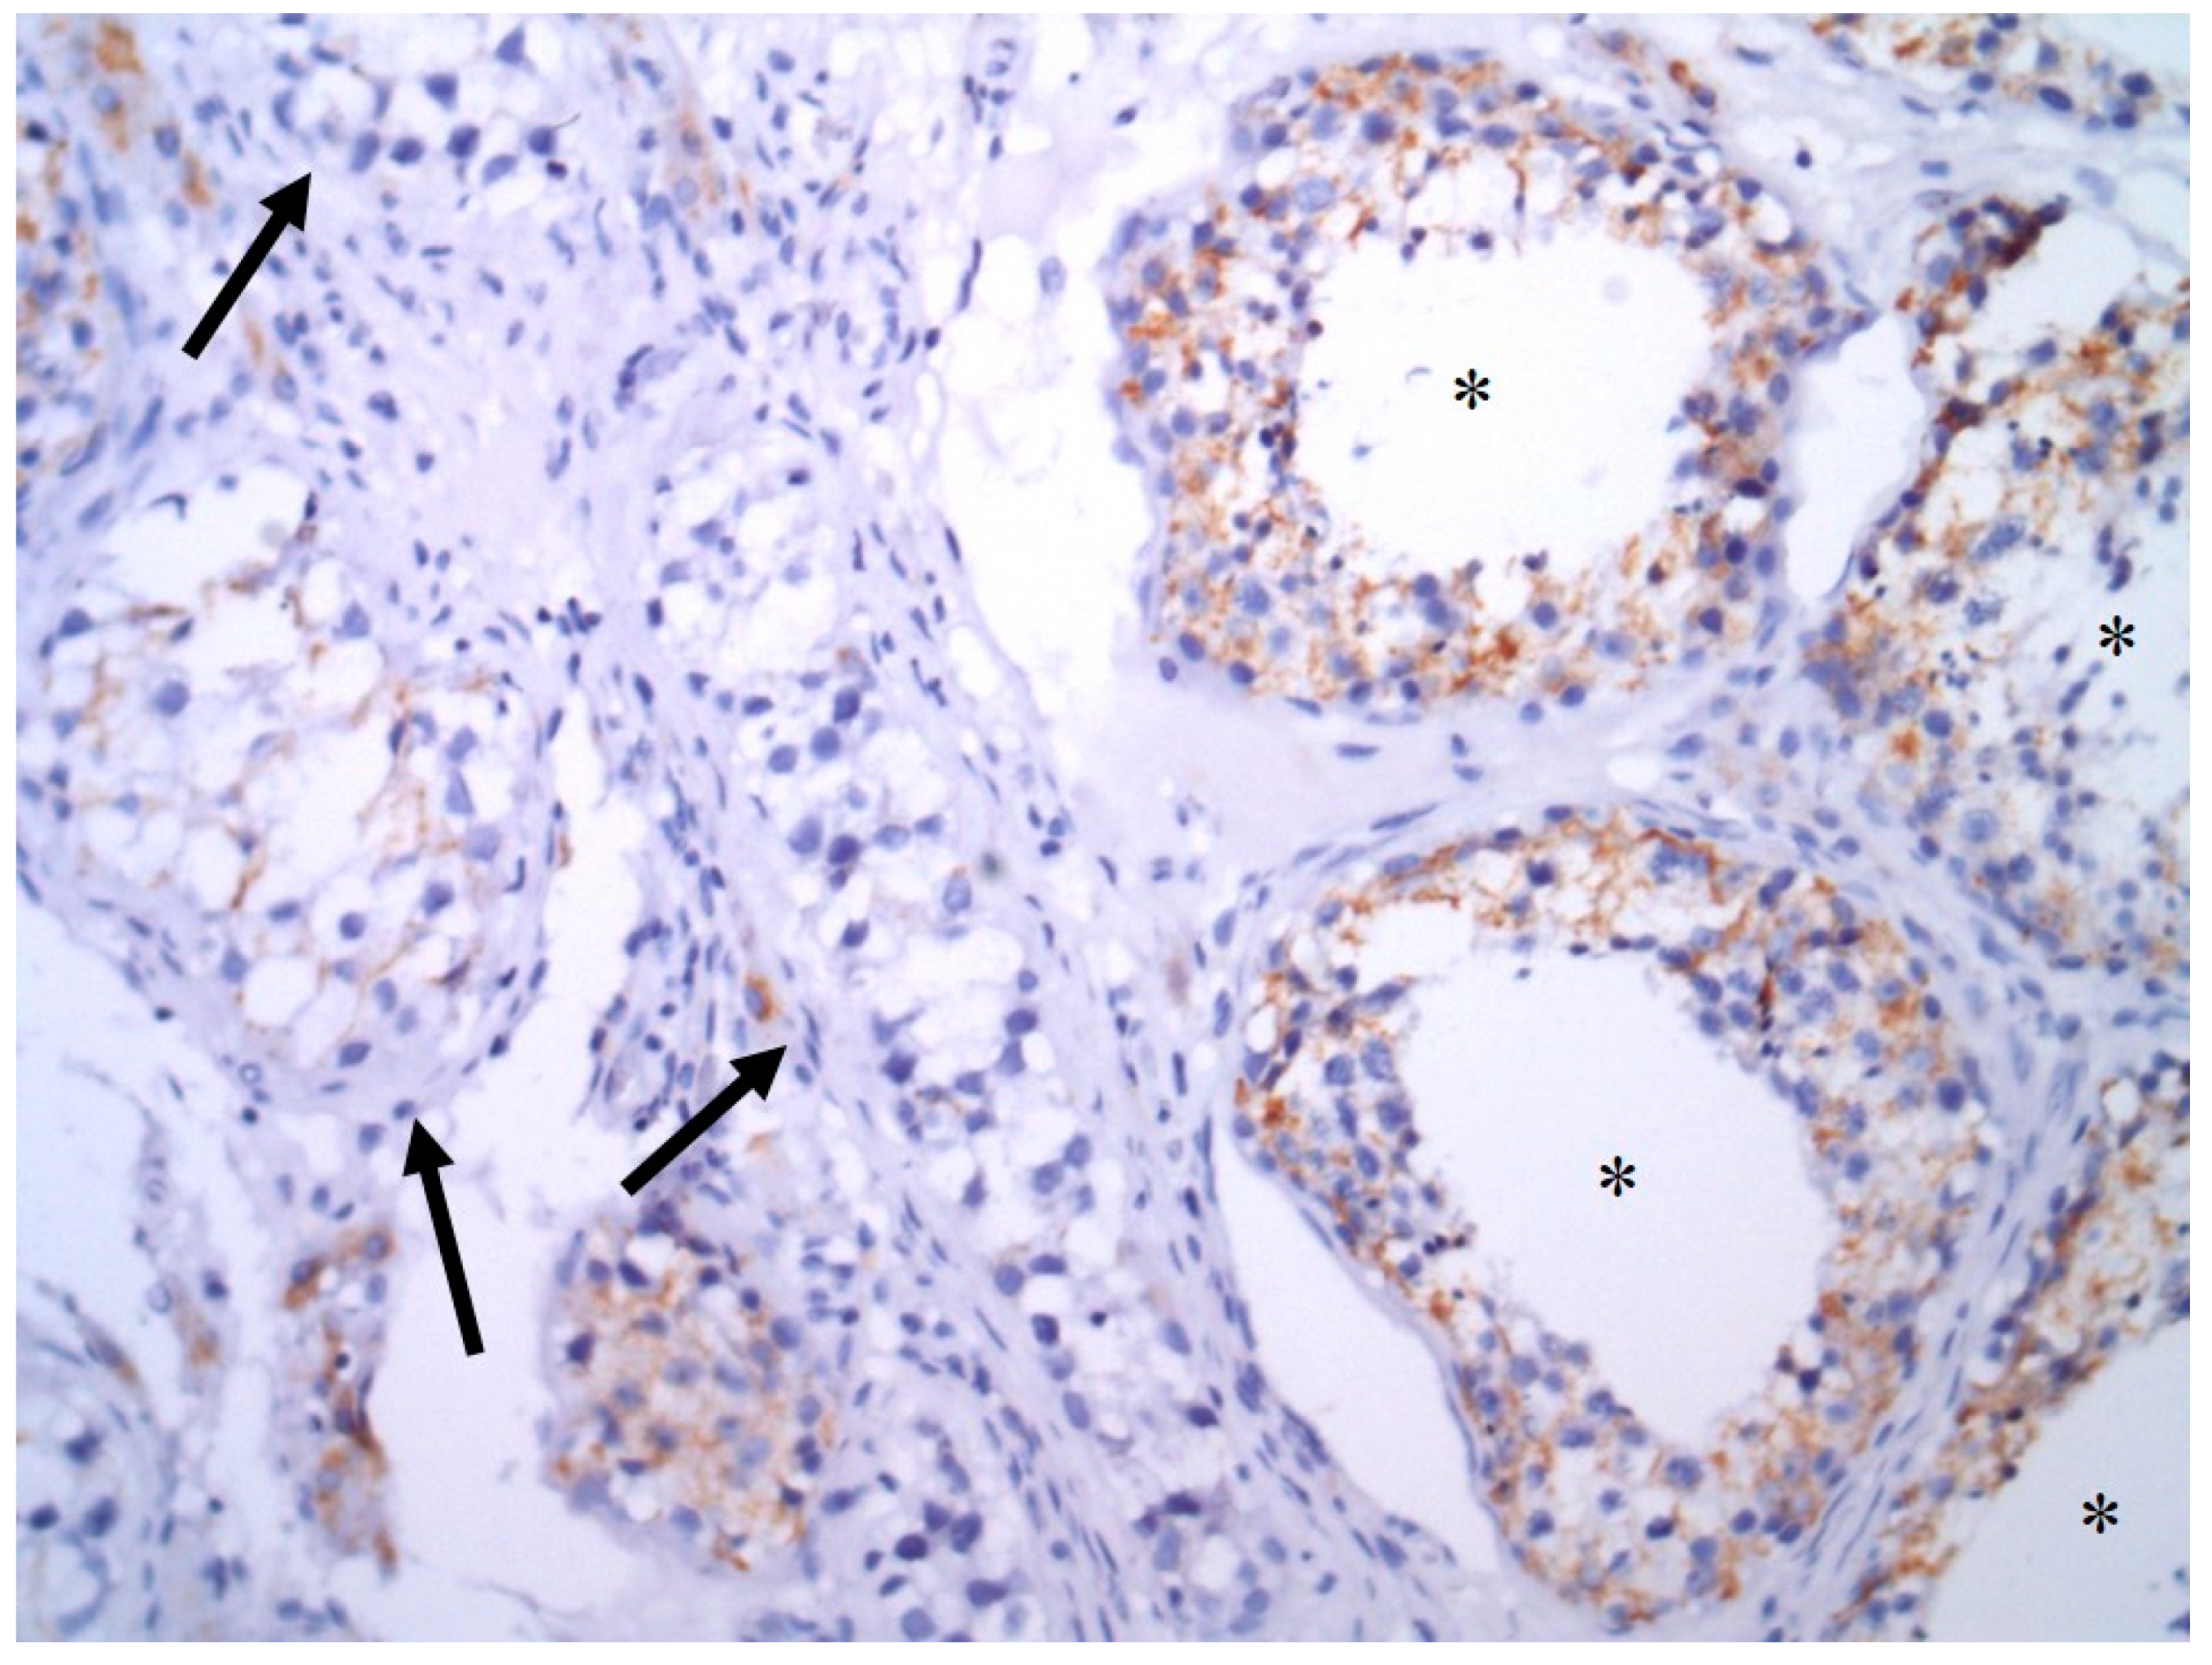

3.2. AIF Expression in GCTs

| Histologic Subtype | Number of Samples (N) | Mean QS | SEM | Median | p-Value a | Low QS b | High QS c | p-Value a | ||

|---|---|---|---|---|---|---|---|---|---|---|

| N | % | N | % | |||||||

| Normal testis | 64 | 12.77 | 0.65 | 13.5 | NA | 14 | 21.9 | 50 | 78.1 | NA |

| Germ cell tumors | 216 | 4.80 | 0.31 | 4.0 | <0.0001 | 174 | 80.6 | 42 | 19.4 | <0.0001 |

| Seminoma | 70 | 3.94 | 0.55 | 2.1 | <0.0001 | 57 | 81.4 | 13 | 18.6 | <0.0001 |

| Embryonal carcinoma | 128 | 5.17 | 0.40 | 4.0 | <0.0001 | 102 | 79.7 | 26 | 20.3 | <0.0001 |

| Yolk sac tumor | 26 | 4.73 | 0.83 | 4.0 | <0.0001 | 23 | 88.5 | 3 | 11.5 | <0.0001 |

| Choriocarcinoma | 12 | 0.17 | 0.17 | 0.0 | <0.0001 | 12 | 100.0 | 0 | 0.0 | <0.0001 |

| Teratoma (epT) | 21 | 1.62 | 0.65 | 0.0 | <0.0001 | 21 | 100.0 | 0 | 0.0 | <0.0001 |

| Teratoma (mesT) | 32 | 0.47 | 0.38 | 0.1 | <0.0001 | 31 | 96.9 | 1 | 3.1 | <0.0001 |

| GCNIS | 62 | 5.66 | 0.67 | 3.0 | <0.0001 | 50 | 80.6 | 12 | 19.4 | <0.0001 |